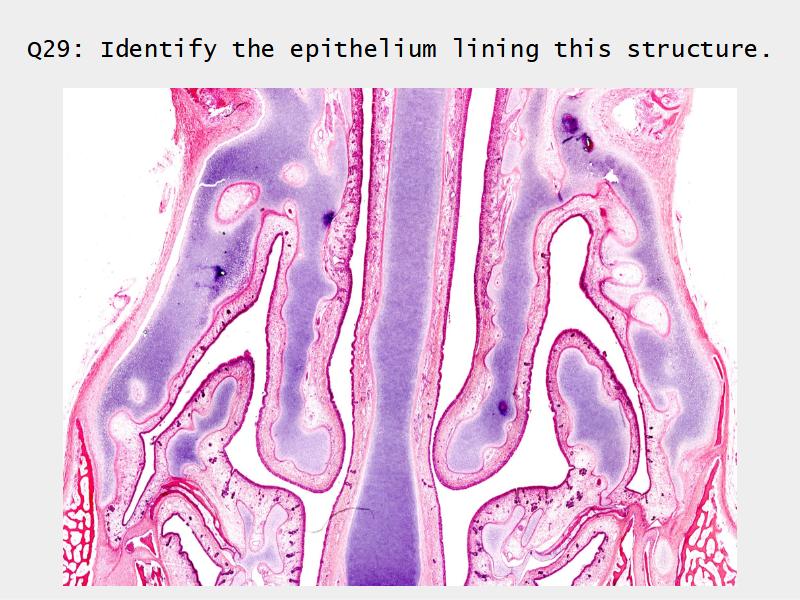

Slides: Respiratory System

- Slide 108: Olfactory epithelium

Olfactory epithelium

Function of the nasal cavity?

Function of the nasal cavity?

- Warm

- Moisture

- Filter

- Smell